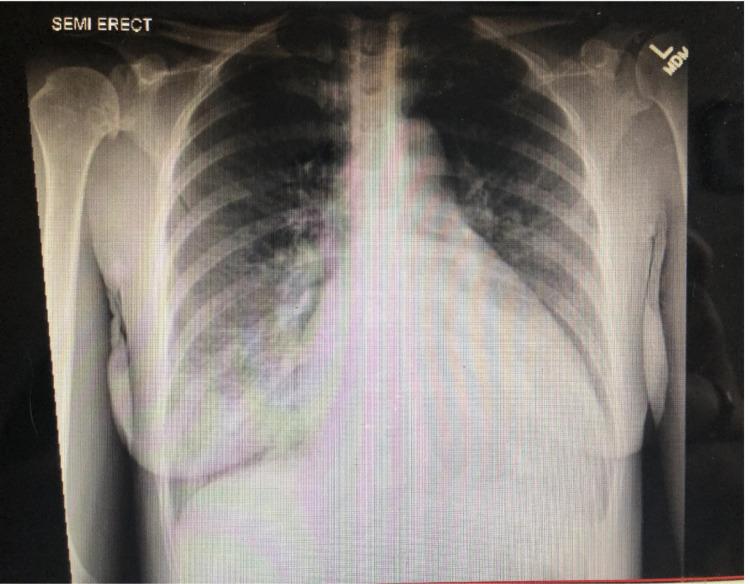

Quadricuspid aortic valve (QAV) is a rare congenital cardiac anomaly. A normal aortic valve has three cusps, but cases of unicuspid, bicuspid, and quadricuspid aortic valves have been reported. Although QAV usually appears as an isolated congenital anomaly, it may also be associated with other heart conditions. In comparison to the bicuspid aortic valve (BAV) that results in aortic stenosis by the early 50s due to age-related early calcification, this case series suggests that patients with QAV are likely to develop moderate to severe aortic regurgitation in their late 40s or early 50s. Most patients with QAV require tricuspidalization, which is the preferred method for QAV surgical repair, especially in patients with associated aortic regurgitation. The condition was previously diagnosed intraoperatively or postpartum. Today, with imaging modalities like transthoracic echocardiography (TTE), transesophageal echocardiography (TEE), and cardiac magnetic resonance imaging, more cases of QAV have been diagnosed in asymptomatic individuals. We present a case series of a previously healthy 49-year-old male and a 47-year-old female who had similar presentations of acute congestive heart failure (CHF). An echocardiogram confirmed that both patients had heart failure with reduced ejection fraction, dilated cardiomyopathy, QAV, and moderate to severe aortic valve regurgitation on echocardiogram. The male patient had an ejection fraction (EF) of 30-35% and a QAV with partial fusion of the leaflets, resulting in a functionally bicuspid aortic valve, while the female patient had an EF of 25-30% with what appears to be a type III QAV according to Nakamura et al. classification. The purpose of this case series is to highlight another potential late complication of congenital QAV.

四叶式主动脉瓣(QAV)是一种罕见的先天性心脏异常。正常的主动脉瓣有三个瓣叶,但也曾有单叶式、二叶式和四叶式主动脉瓣的病例报道。虽然QAV通常表现为孤立的先天性异常,但它也可能与其他心脏疾病相关。与二叶式主动脉瓣(BAV)相比,后者由于与年龄相关的早期钙化,在50岁出头时就会导致主动脉狭窄,而本病例系列表明,QAV患者在40多岁后期或50岁出头时可能会出现中度至重度主动脉瓣反流。大多数QAV患者需要进行三叶化手术,这是QAV手术修复的首选方法,尤其是对于伴有主动脉瓣反流的患者。该疾病以前是在术中或产后诊断出来的。如今,借助经胸超声心动图(TTE)、经食管超声心动图(TEE)和心脏磁共振成像等影像学检查手段,更多无症状个体中的QAV病例得以确诊。我们呈现了一个病例系列,其中包括一名49岁的既往健康男性和一名47岁的女性,他们都有类似的急性充血性心力衰竭(CHF)表现。超声心动图证实,两名患者均患有射血分数降低的心力衰竭、扩张型心肌病、QAV以及超声心动图显示的中度至重度主动脉瓣反流。男性患者的射血分数(EF)为30 - 35%,其QAV瓣叶部分融合,形成功能性二叶式主动脉瓣,而根据中村等人的分类,女性患者的EF为25 - 30%,似乎是III型QAV。本病例系列的目的是强调先天性QAV另一种潜在的晚期并发症。